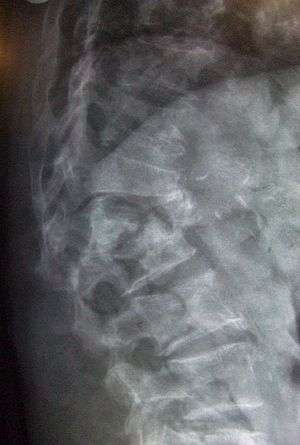

Conventional radiography

Conventional radiography is useful, both by itself and in conjunction with CT or MRI, for detecting complications of osteopenia (reduced bone mass; pre-osteoporosis), such as fractures; for differential diagnosis of osteopenia; or for follow-up examinations in specific clinical settings, such as soft tissue calcifications, secondary hyperparathyroidism, or osteomalacia in renal osteodystrophy. However, radiography is relatively insensitive to detection of early disease and requires a substantial amount of bone loss (about 30%) to be apparent on X-ray images.

The main radiographic features of generalized osteoporosis are cortical thinning and increased radiolucency. Frequent complications of osteoporosis are vertebral fractures for which spinal radiography can help considerably in diagnosis and follow-up. Vertebral height measurements can objectively be made using plain-film X-rays by using several methods such as height loss together with area reduction, particularly when looking at vertical deformity in T4-L4, or by determining a spinal fracture index that takes into account the number of vertebrae involved. Involvement of multiple vertebral bodies leads to kyphosis of the thoracic spine, leading to what is known as dowager's hump.